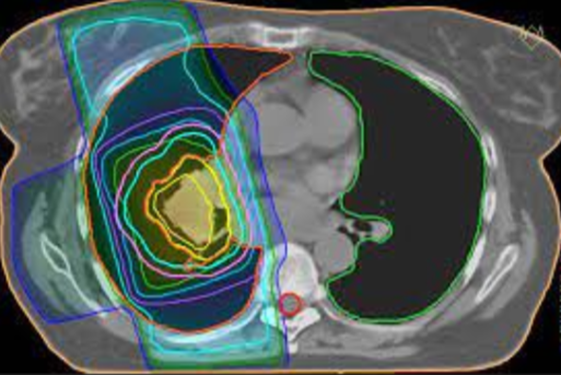

Behandlingen må utføres presist og skånsomt for å unngå skade på friskt vev. Derfor lages det individuelle doseplaner for hver enkelt pasient, se figuren under